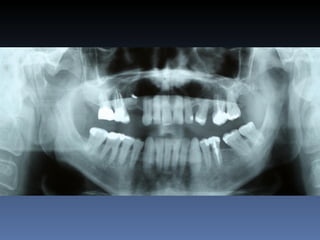

BOX 2

Sebastião Moreira Souza

Idade – 49 anos

Sexo – Masculino

Raça – Caucasiana

ASA – II

Data- 23-04-2012

Diagnóstico: Desdentado total maxila

Plano de tratamento:          Reabilitação com 6 blocos

“onlay” e “sinus-llift” bilateral, provenientes de Úmero

fresco-congelado (FFB); reabertura para instalação

de 6 implantes dentários endo-ósseos e reabilitação

protética fixa.